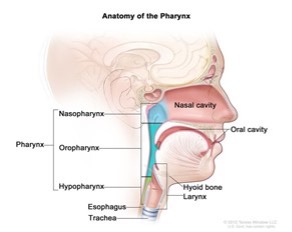

The oropharynx is the part of the body that includes the mouth and throat. In simple terms, it is a tube lined with muscular tissues. This includes the back third of the tongue, the soft palate, the side and back walls of the throat, and the tonsils. These muscles help us to eat, talk, and breathe. They also help to keep the airway open, especially during sleep.

When the muscles of the oropharynx are weak, they may disrupt the flow of air and creating problems with speech, swallowing, and breathing. This is evident with mouth breathers and snoring while sleeping. During sleep, the muscle (a floppy tongue) collapses and the airway becomes blocked. This is the gasping effect as happens during sleep apnea. A weak and floppy tongue falls back into the throat and create an obstruction.

Sleep Apnea: This disorder causes a breathing to repeatedly stop and start while asleep. Most common cause is the muscles (in the throat) irregularly relax and block the airway.